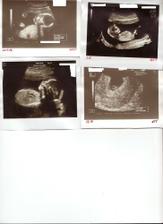

3.12. NT screening - na UTZ je vidět nedokončená CHA disociace (může znamenat i poškození plodu) další KO 17.12.

17.12. UTZ v Podolí. Byla tam se mnou i mamka a moc si to užívala. CHA disociace se uzavírá, vše bude snad vpořádku.

28.1. podrobný UTZ v Podolí - vše vypadá dobře, že miminko je zdravé

21.3. 3D UTZ v Gennetu byl nezapomenutelným zážitkem a ty peníze za to určitě stojí. Asi půlhodinový utz, kde jsme viděli naší princeznu. Nejdříve měla obličej přikrytý rukama i nohama, ale pak se ukázala - usmívala se, zívala, polykala plodovku. Jen pohlaví nám moc odhalit nechtěla. Stydlivka.